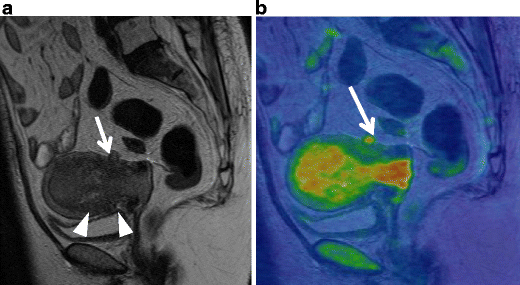

Serous carcinoma in a 55-year-old female. a Sagittal T2-weighted image demonstrates an endometrial tumor of decreased intensity occupying the endometrial cavity, and protruding into the external cervical os. Note the endometrial-myometrial border in both the corpus and cervix is diffusely obscured, suggesting myometrial invasion of the tumor (arrowheads). There is a small implant on the posterior serosal surface of the uterus (arrow). b Fusion image of DWI onto T2-weighted image exhibits increased intensity corresponding to the tumor in the endometrial cavity. The implantation on the posterior wall is also clearly demonstrated with excellent tissue contrast (arrowhead)

Endometrioid carcinoma in 69-year-old woman. a T2-weighted image demonstrates an ill-defined myometrial mass of decreased intensity (arrows). b Fusion image with DWI onto T2-weighted image shows increased intensity in the myometrial mass, which represents endometrioid carcinoma infiltrating into the myometrium